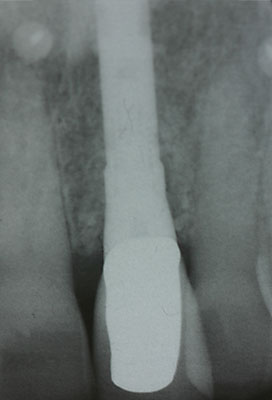

Fall: Einzelzahnlücke nach Zahnextraktion